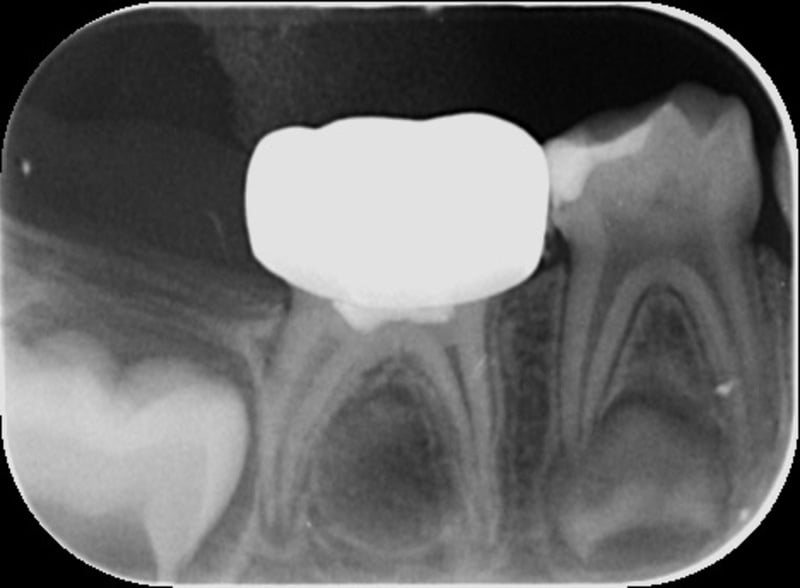

Foi realizado um exame clínico e radiológico inicial (fig. 1 a 3), tendo sido diagnosticada, entre outras lesões de cárie, uma lesão de cárie profunda com atingimento pulpar no segundo molar temporário inferior direito (fig. 3). Foi proposta a realização de uma pulpotomia com agregado trióxido mineral (MTA) e a colocação de uma coroa pré-formada. As várias possibilidades restauradoras foram apresentadas e discutidas com os pais, que decidiram optar pela colocação de uma coroa pré-formada de zircónia, por motivos estéticos.

No exame clínico e radiográfico realizado seis meses após o tratamento, não foi referido nenhum sintoma nem foram observados sinais indicadores de fracasso (fig. 10 e 11). Na radiografia periapical é possível observar a presença de pontes de dentina à entrada dos canais radiculares (fig. 11).

A utilização de MTA em pulpotomias de molares temporários apresenta uma elevadíssima taxa de sucesso observável no plano radiográfico pela ausência de imagens radiolúcidas na região apical e da furca radicular, e pela presença de pontes de dentina na entrada dos canais radiculares.7,8,9